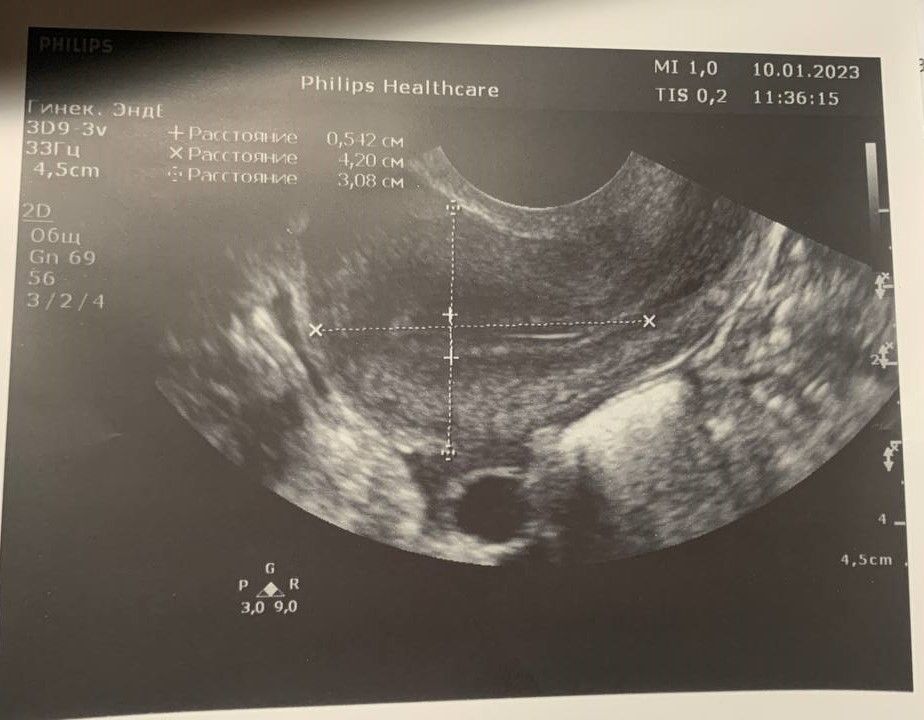

9.01 поздно вечером был ПА, 10.01 в 11 утра была на УЗИ, сказали, что овуляция уже была. Желтое тело 15,7 мм. До этого ПА не было. Мы не успели? или есть шанс? Цикл у меня 28-32 дня, в прошлом цикле была бхб. Планируем всего 2-ой цикл)

Я тоже пришла, сказала была овуля(ЖТ 19мм)(Эндо 8), когда узнаю если месячные пойдёт, а они пойдут , так как хгч 1.20 😭